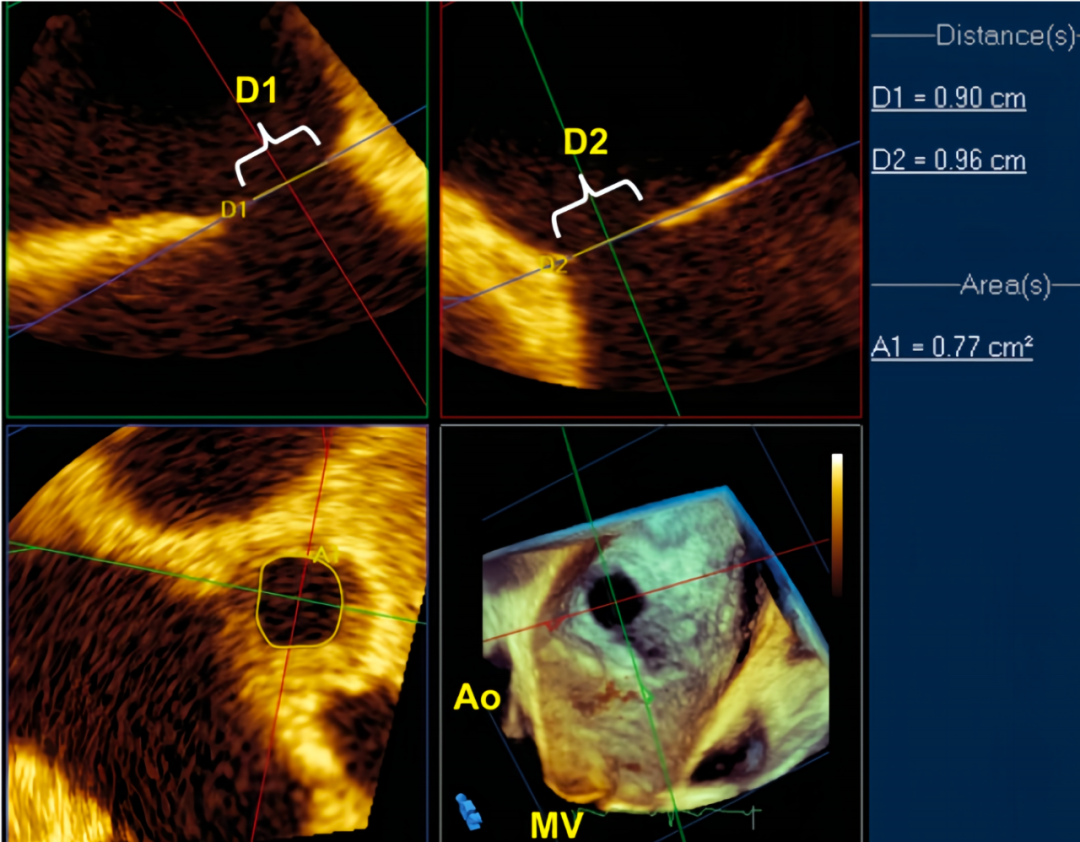

当然,大家不要遗忘我们还有一个游离工具,那就是实时三维超声心动图,包括经胸及经食管实时三维超声心动图(RT 3D TEE),由于后者与ASD的诊疗关系更为密切。

RT 3D TEE可以更好的确定ASD的数目、形态和位置,并可采用左房观或右房观,确定缺损位置与周围组织结构的空间关系,是经胸超声检查的重要补充。RT 3D TEE甚至可以修正既往检查结果,从而影响或改变患者治疗方式。